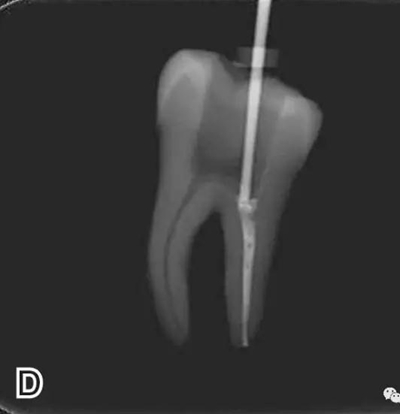

3、試尖

選擇非標(biāo)準(zhǔn)牙膠尖(如0.04、0.06 錐度牙膠尖)作為主尖,型號一般與根管預(yù)備最大號的器械型號一致,能到達(dá)距根尖0.5~1 mm 處,主尖尖段與根管壁緊密接觸。拍試尖X 線片進(jìn)行確認(rèn)(圖3)。

圖3 試尖,A.試主尖 B.拍試尖X片